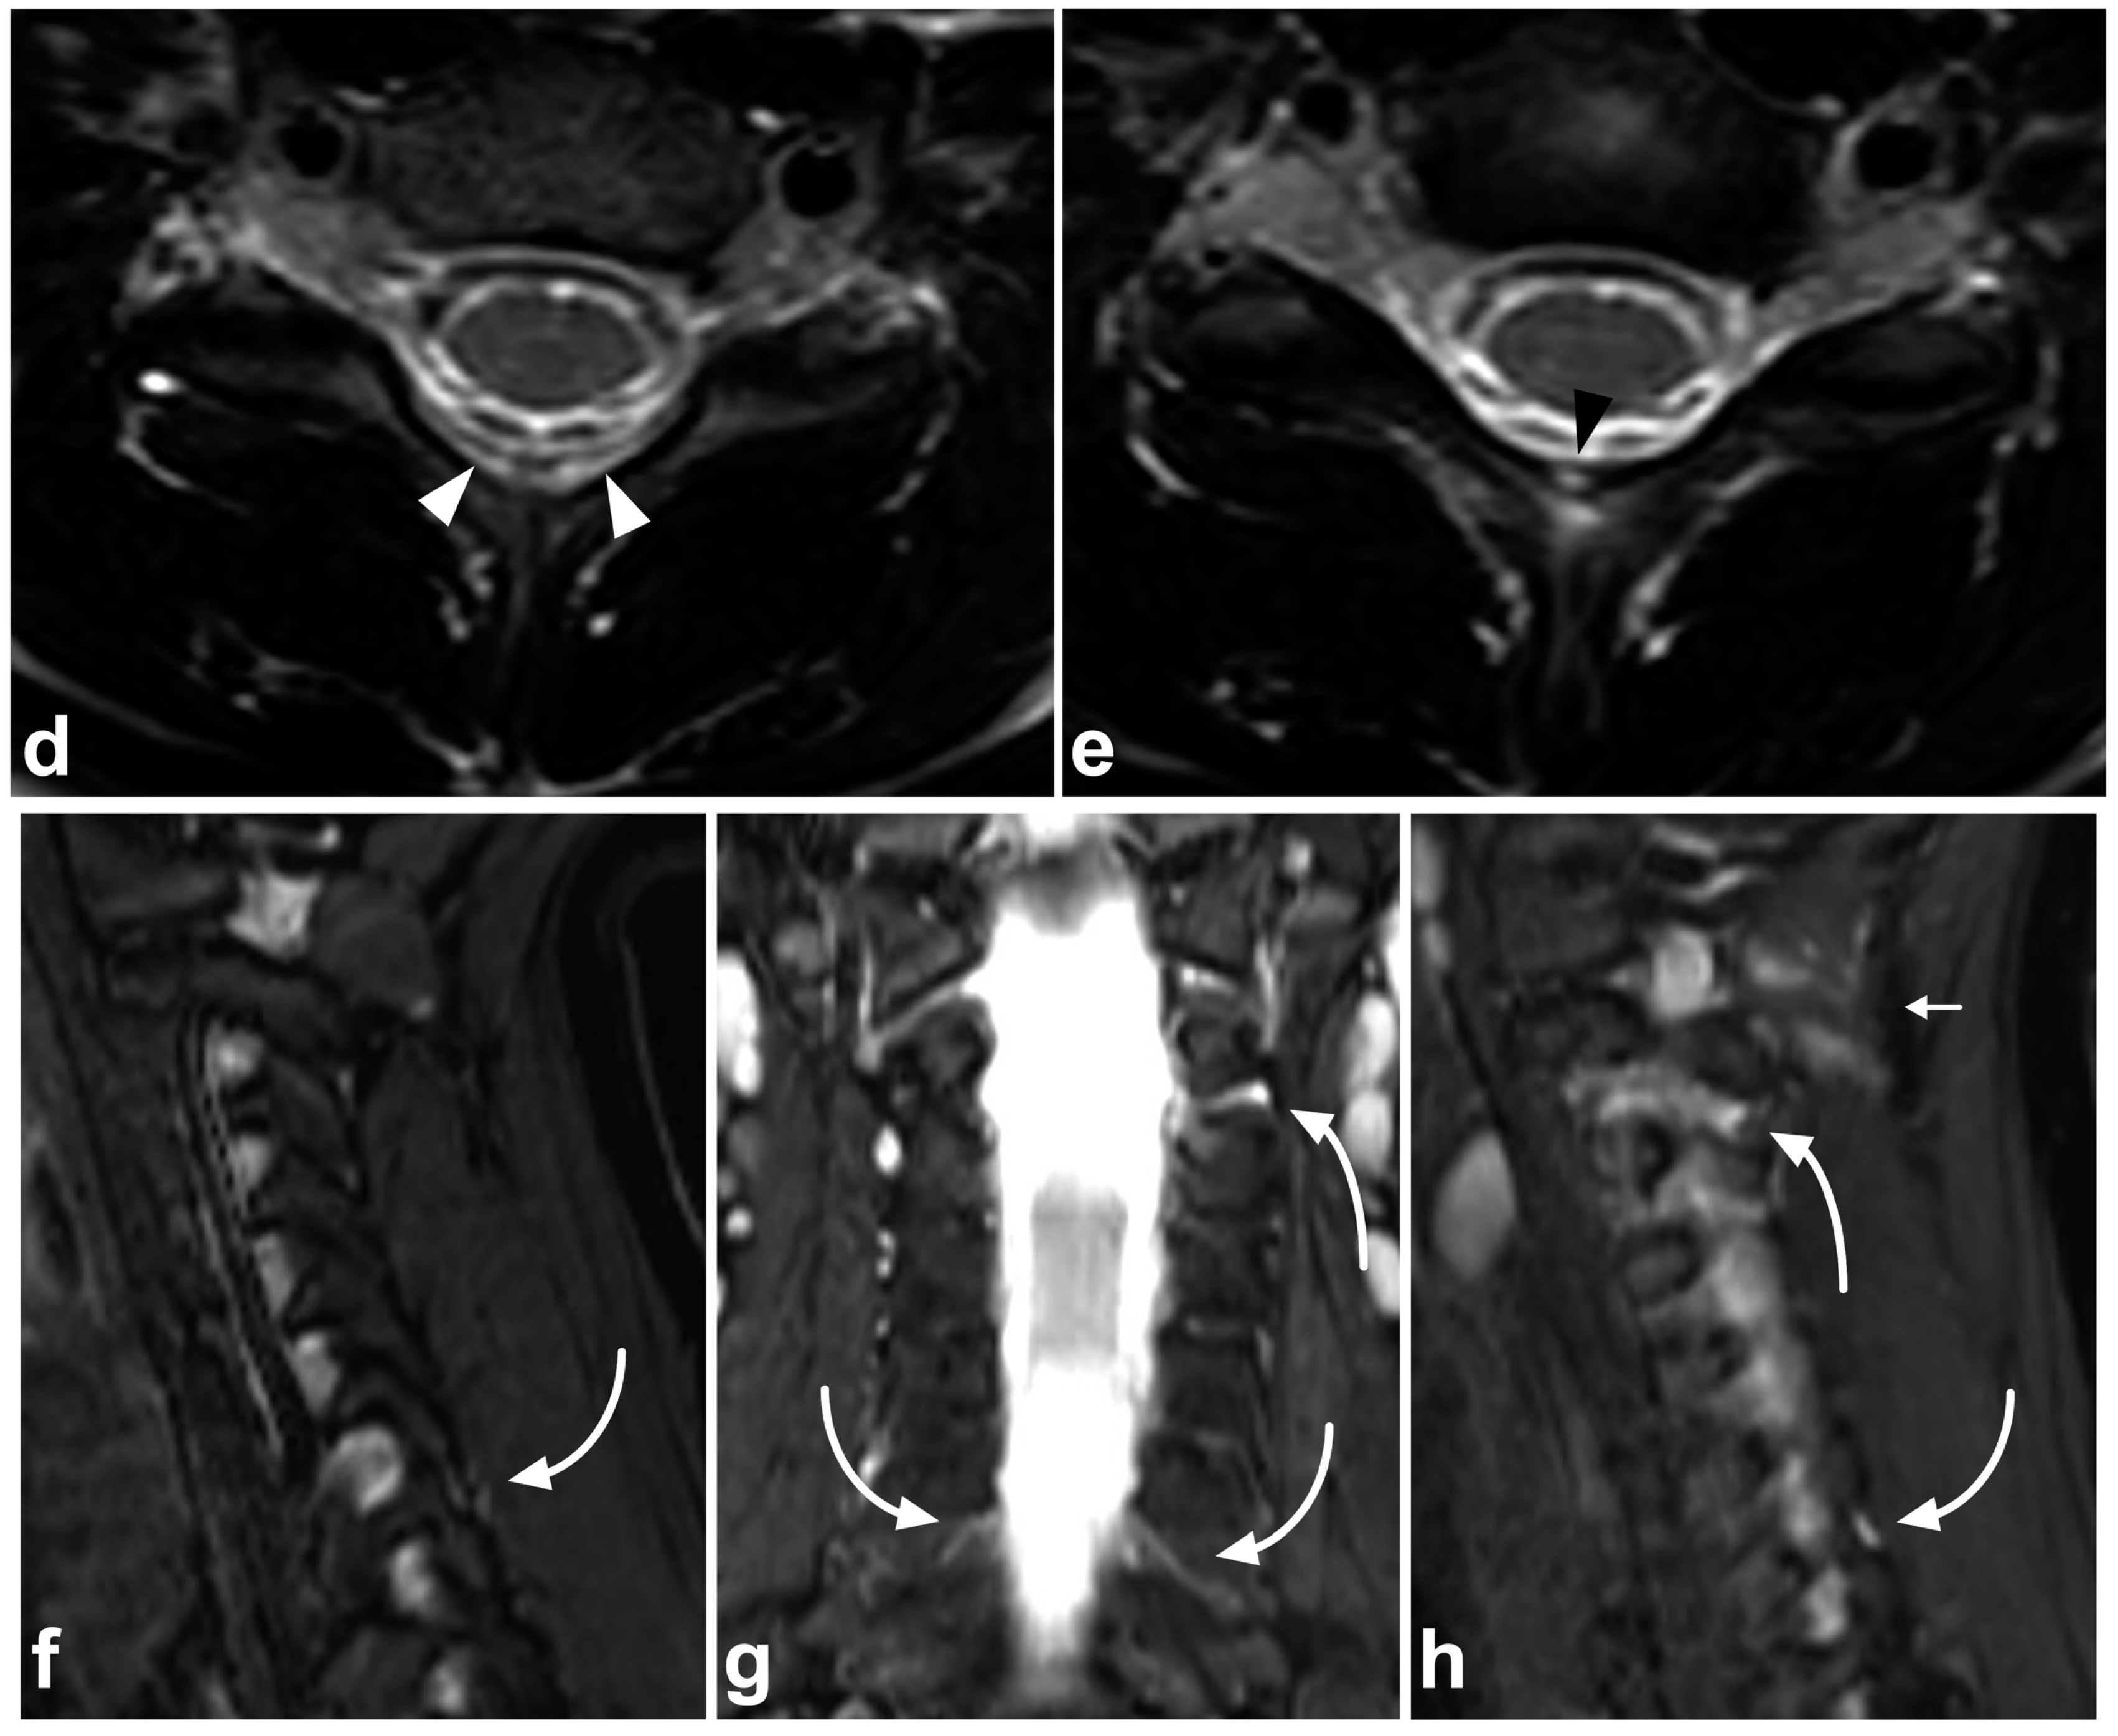

6. Spinal Cord Injuries

7. Physiological Findings and Pitfalls